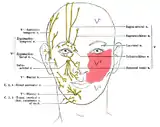

Sensory branches

The ophthalmic, maxillary and mandibular branches leave the skull through three separate foramina: the superior orbital fissure, the foramen rotundum and the foramen ovale, respectively. The ophthalmic nerve (V1) carries sensory information from the scalp and forehead, the upper eyelid, the conjunctiva and cornea of the eye, the nose (including the tip of the nose, except alae nasi), the nasal mucosa, the frontal sinuses and parts of the meninges (the dura and blood vessels). The maxillary nerve (V2) carries sensory information from the lower eyelid and cheek, the nares and upper lip, the upper teeth and gums, the nasal mucosa, the palate and roof of the pharynx, the maxillary, ethmoid and sphenoid sinuses and parts of the meninges. The mandibular nerve (V3) carries sensory information from the lower lip, the lower teeth and gums, the chin and jaw (except the angle of the jaw, which is supplied by C2-C3), parts of the external ear and parts of the meninges. The mandibular nerve carries touch-position and pain-temperature sensations from the mouth. Although it does not carry taste sensation (the chorda tympani is responsible for taste), one of its branches—the lingual nerve—carries sensation from the tongue.

Dermatomes

The areas of cutaneous distribution (dermatomes) of the three sensory branches of the trigeminal nerve have sharp borders with relatively little overlap (unlike dermatomes in the rest of the body, which have considerable overlap). The injection of a local anesthetic, such as lidocaine, results in the complete loss of sensation from well-defined areas of the face and mouth. For example, teeth on one side of the jaw can be numbed by injecting the mandibular nerve. Occasionally, injury or disease processes may affect two (or all three) branches of the trigeminal nerve; in these cases, the involved branches may be termed:

- V1/V2 distribution – Referring to the ophthalmic and maxillary branches

- V2/V3 distribution – Referring to the maxillary and mandibular branches

- V1-V3 distribution – Referring to all three branches

Diagram of facial sensory nerves (front view)

Diagram of facial sensory nerves (front view) Trigeminal nerve in yellow